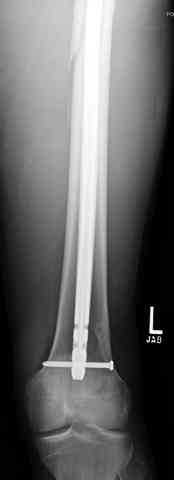

Здесь представлены несколько случаев лечения огнестрельного перелома

1 Проксимальный перелом бедра, антеградный гвоздь

С некоторым опозданием сообщу, больной был прооперирован, МОС пластиной. Ни каких инфекционных осложнений не наблюдалось. На данный момент больной передвигается самостоятельно, без дополнительной опоры.Слегка прихрамывая на правую ногу.